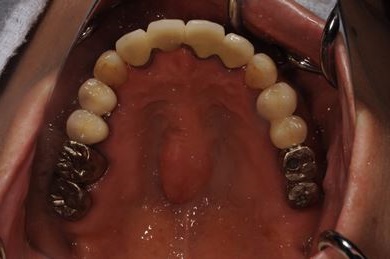

骨再生スピードインプラント治療+セラミック治療

| 治療方針 | 骨再生法によりインプラント治療を可能にする。抜歯と同時にインプラント埋入を行い、治療期間を短縮する。 | ||||||||||||||||||||||||||||||||

| 治療内容 | インプラント3本(抜歯即日スピードインプラント、GBR)、メタルボンドセラミッククラウン4本 | ||||||||||||||||||||||||||||||||

| 総治療費 | 1,509,902円 | ||||||||||||||||||||||||||||||||

| 治療期間 | 1年5ヶ月 |